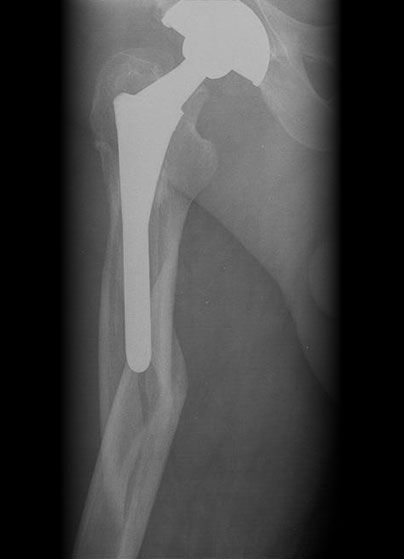

Failed THR

Revised THR